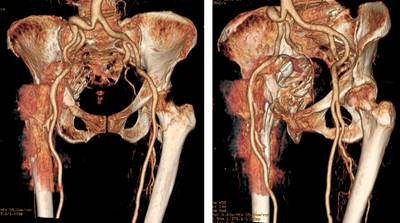

Con los hallazgos encontrados se solicitan estudios de imagen adicionales (Figuras 2 y 3).

Figura 2: Tomografía de pelvis, se observa migración medial intrapélvica de componente acetabular y fractura acetabular transversa: A) corte coronal, B) axial y C) sagital.

Figura 3: Reconstrucción 3D de tomografía contrastada, se evidencia ausencia de lesión de grandes vasos por migración medial intrapélvica de componente acetabular.